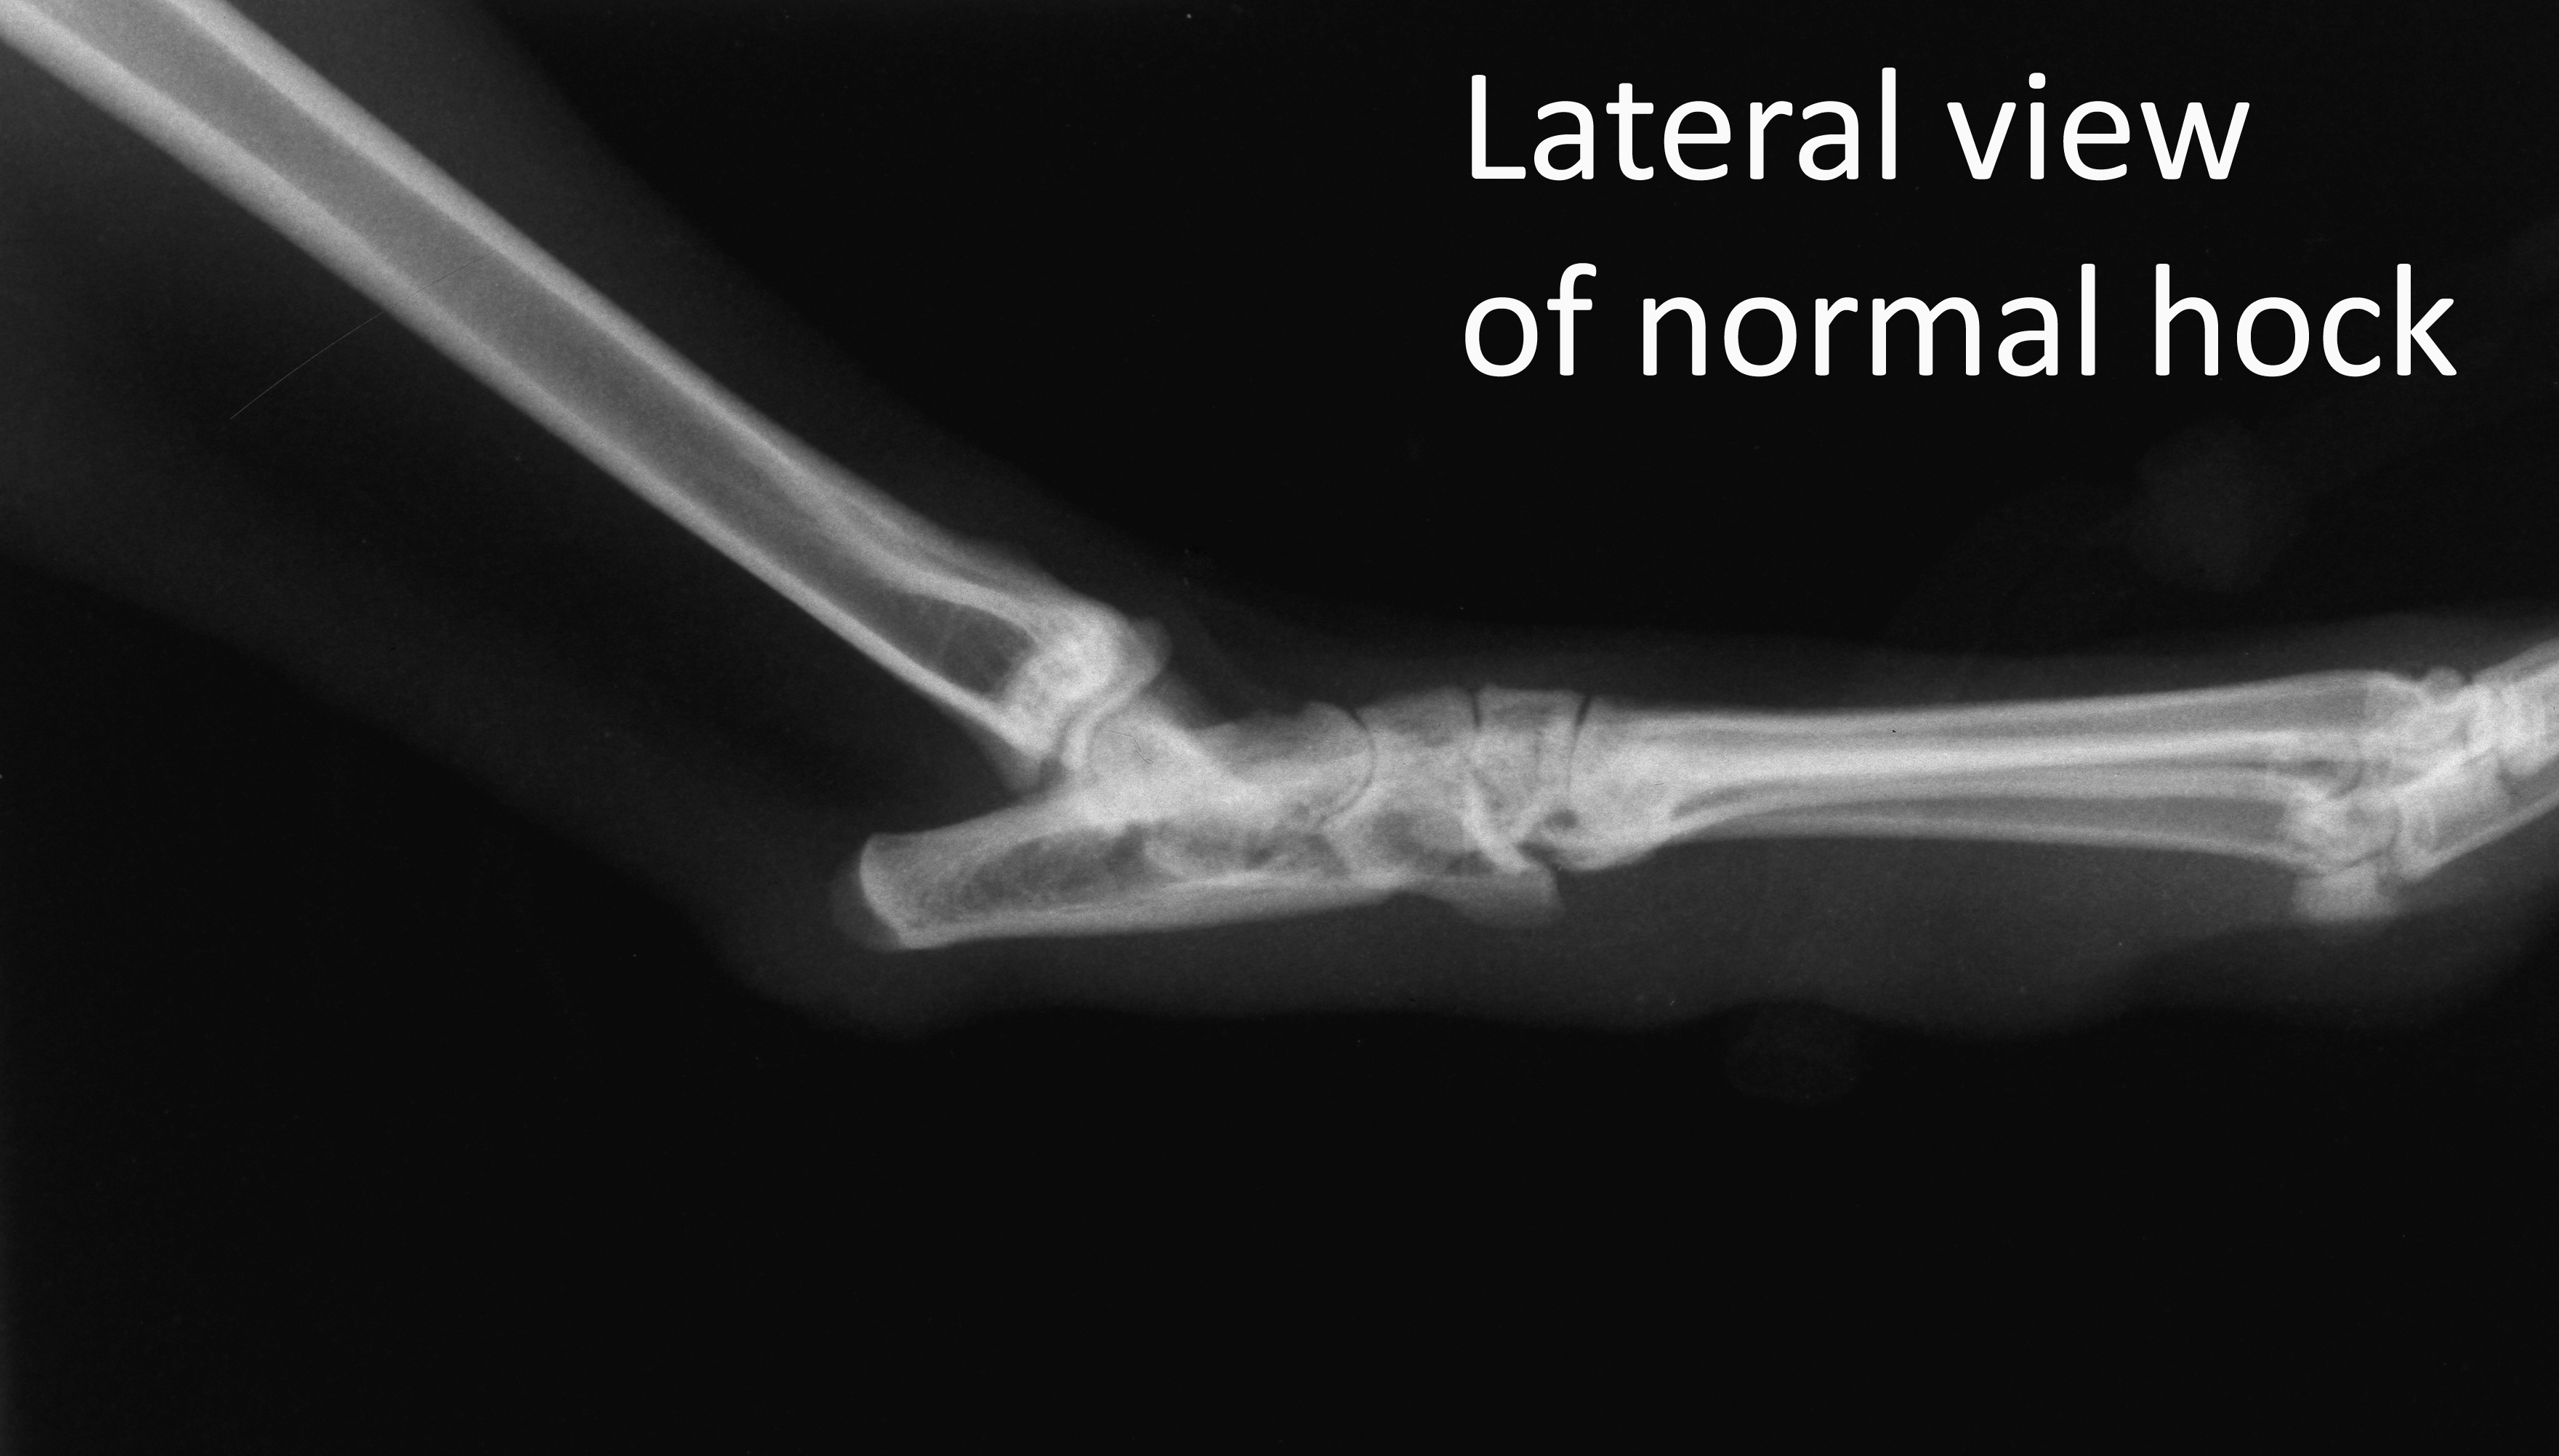

Lateral view of normal hock